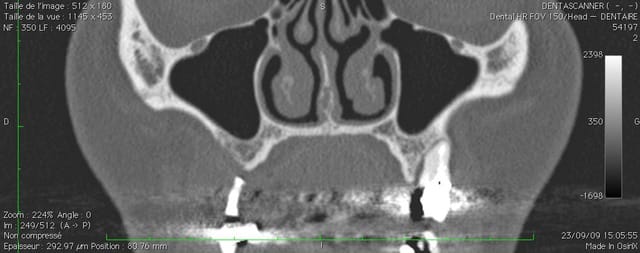

oui ça fait un gros prélèvement, c'est pour un cas particulier ou je dois virer 24, 25 et 26 avec de grosses lésions apicales et latérales, ou je voudrais conserver le maximum de volume osseux pour pouvoir implanter dans de bonnes conditions.

ci joint la pano et les coupes scan.